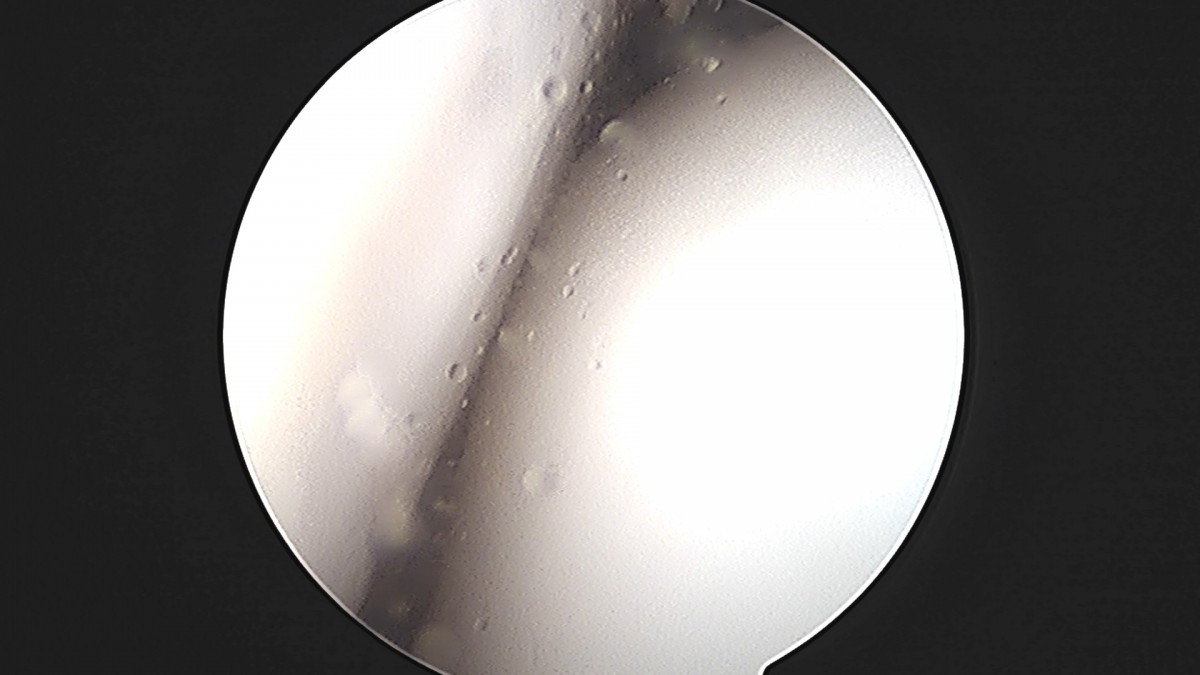

정지영원장님 발목 인대 봉합술 채이O 환자

작성자 최고관리자 댓글 0건 조회 718회 작성일 25-09-16 17:02